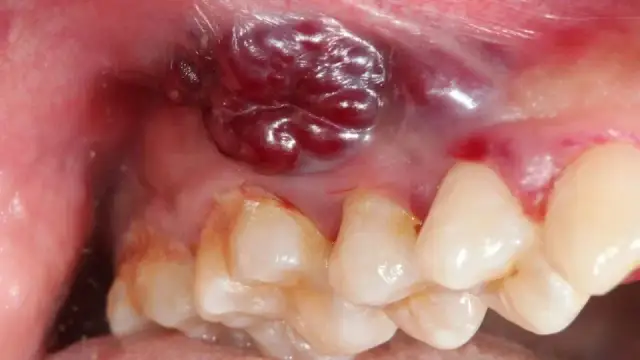

Grzybica jamy ustnej, choć często kojarzona głównie z białym nalotem, ma znacznie szersze spektrum objawów, które mogą wskazywać na jej obecność. Zwróć uwagę na te sygnały, które wysyła Ci Twój organizm. Charakterystyczne jest to, że nalot można zazwyczaj zetrzeć, ale pod nim często kryje się zaczerwieniona i podrażniona tkanka, która może nawet krwawić. Oto pełniejsza lista symptomów:

- Biały, serowaty nalot na języku, podniebieniu, dziąsłach i wewnętrznej stronie policzków. Jest to najbardziej typowy objaw.